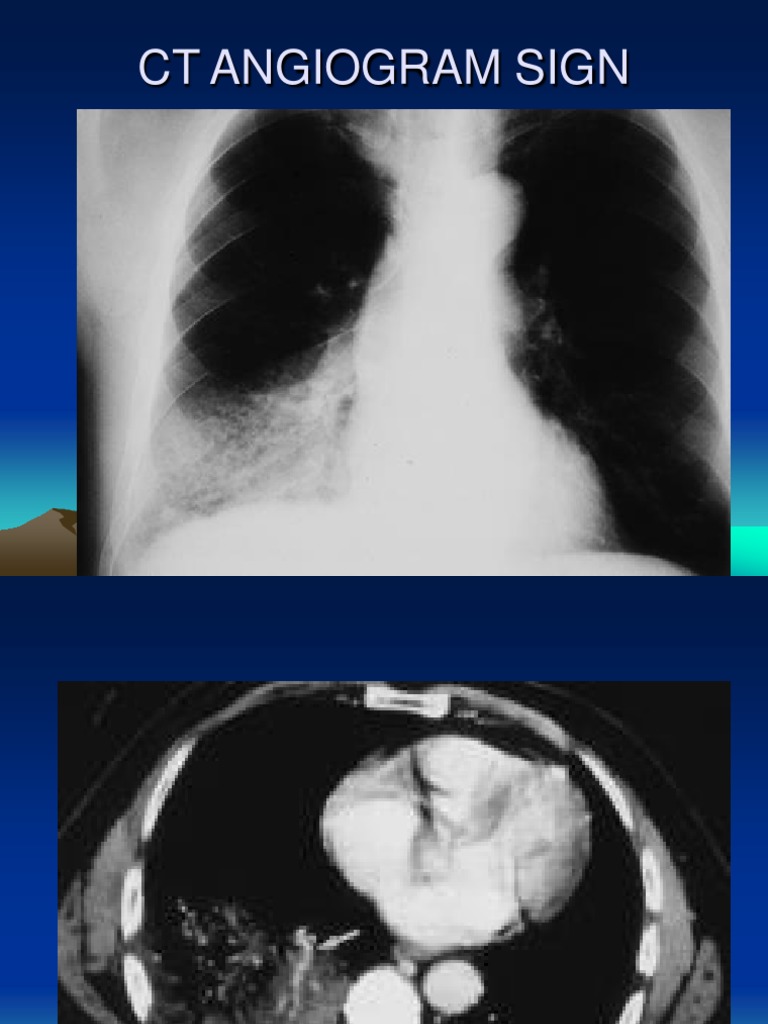

PPT SIGNS IN RADIOLOGY PowerPoint Presentation ID510632 Radiology Signs Pdf pdf | several imaging findings of thoracic diseases have been referred—on chest radiographs or ct scans—to signs, symbols, or. a book review of a textbook that covers 255 radiological signs for various body systems. radiological signs are classical and distinctive abnormalities, characteristic of a disease or a group of similar. Radiologic signs are recognizable, characteristic patterns used. Radiology Signs Pdf.